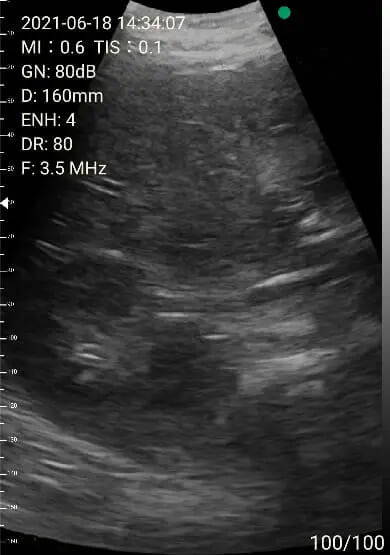

2. Abdomen review

Left lobe of liver

Portal area

Right lobe of liver

Images of thyoid scan on a 35-year-old healthy man.